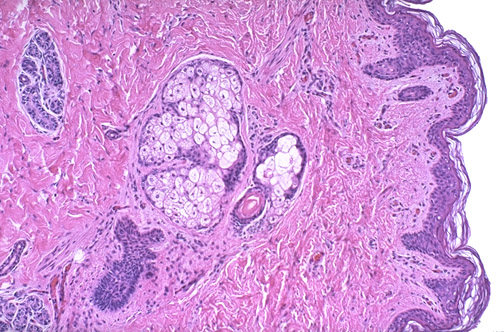

| Normal baby skin is shown here at medium magnification. The keratinizing squamous epithelium is supported by the papillary dermis. Note that the thickness of the baby's epidermis and keratin layer is much thinner than the adult, so that baby is more sensitive to temperature changes and various forms of skin irritants. BE CAREFUL !! There are hair follicles and accompanying adnexae including sebaceous glands and sweat glands in the reticular dermis. |